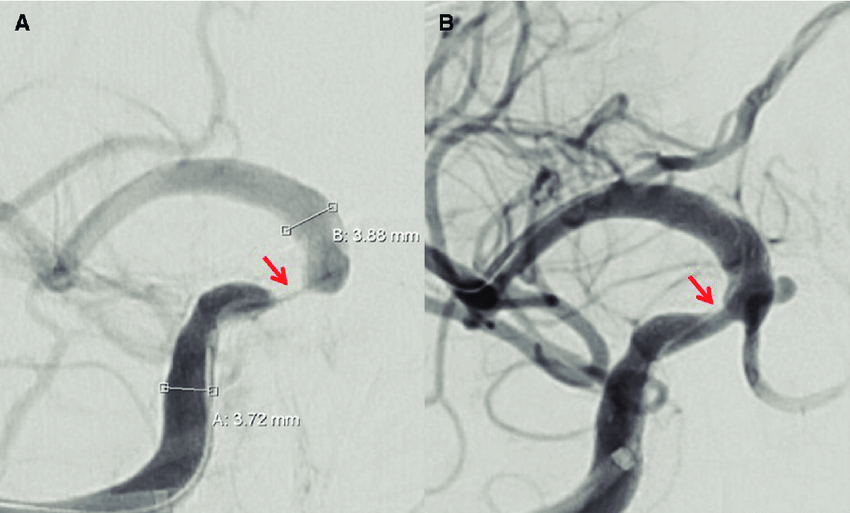

Embolización de la arteria meníngea media en el hematoma subdural subagudo o crónico

Tres ensayos clínicos exploran la utilidad de la embolización de esta arteria en el manejo del hematoma subdural subagudo o crónico, con miras a reducir la tasa de recurrencias y la necesidad de nuevas intervenciones. New England Journal of Medicine, 20 de noviembre de 2024.